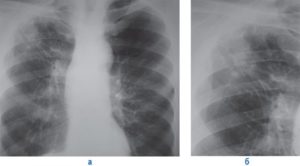

Пневмосклероз – патологический процесс, характеризующийся замещением легочной ткани соединительной, что сопровождается нарушением эластичности и газообмена в пораженных участках.

Процесс носит необратимый характер, постепенно состояние усугубляется за счет разрастания соединительной ткани, которая не способна выполнять функции, возложенные на легочную ткань.

Такой прогрессирующий процесс требует медицинской помощи, потому как без лечения существует угроза инвалидности и даже смерти от осложнений.

Пневмосклероз развивается как исход воспалительных или дистрофических заболеваний легких, чаще встречается у мужчин в возрасте 50 лет и выше.

Выделяют ограниченный и диффузный пневмосклероз, которые различаются по распространенности патологического процесса в легких. Диффузный пневмосклероз протекает значительно тяжелее за счет большого объема поражения легочной ткани.